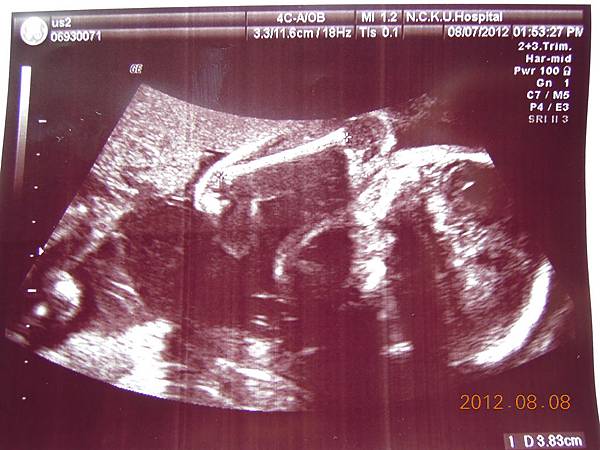

這個好像是逼逼的臉吧~~

這張可以看到他的厚嘴巴~~我回來拿給Horry看,說他跟你的嘴巴一樣ㄟ~~他聽了一直笑~~~